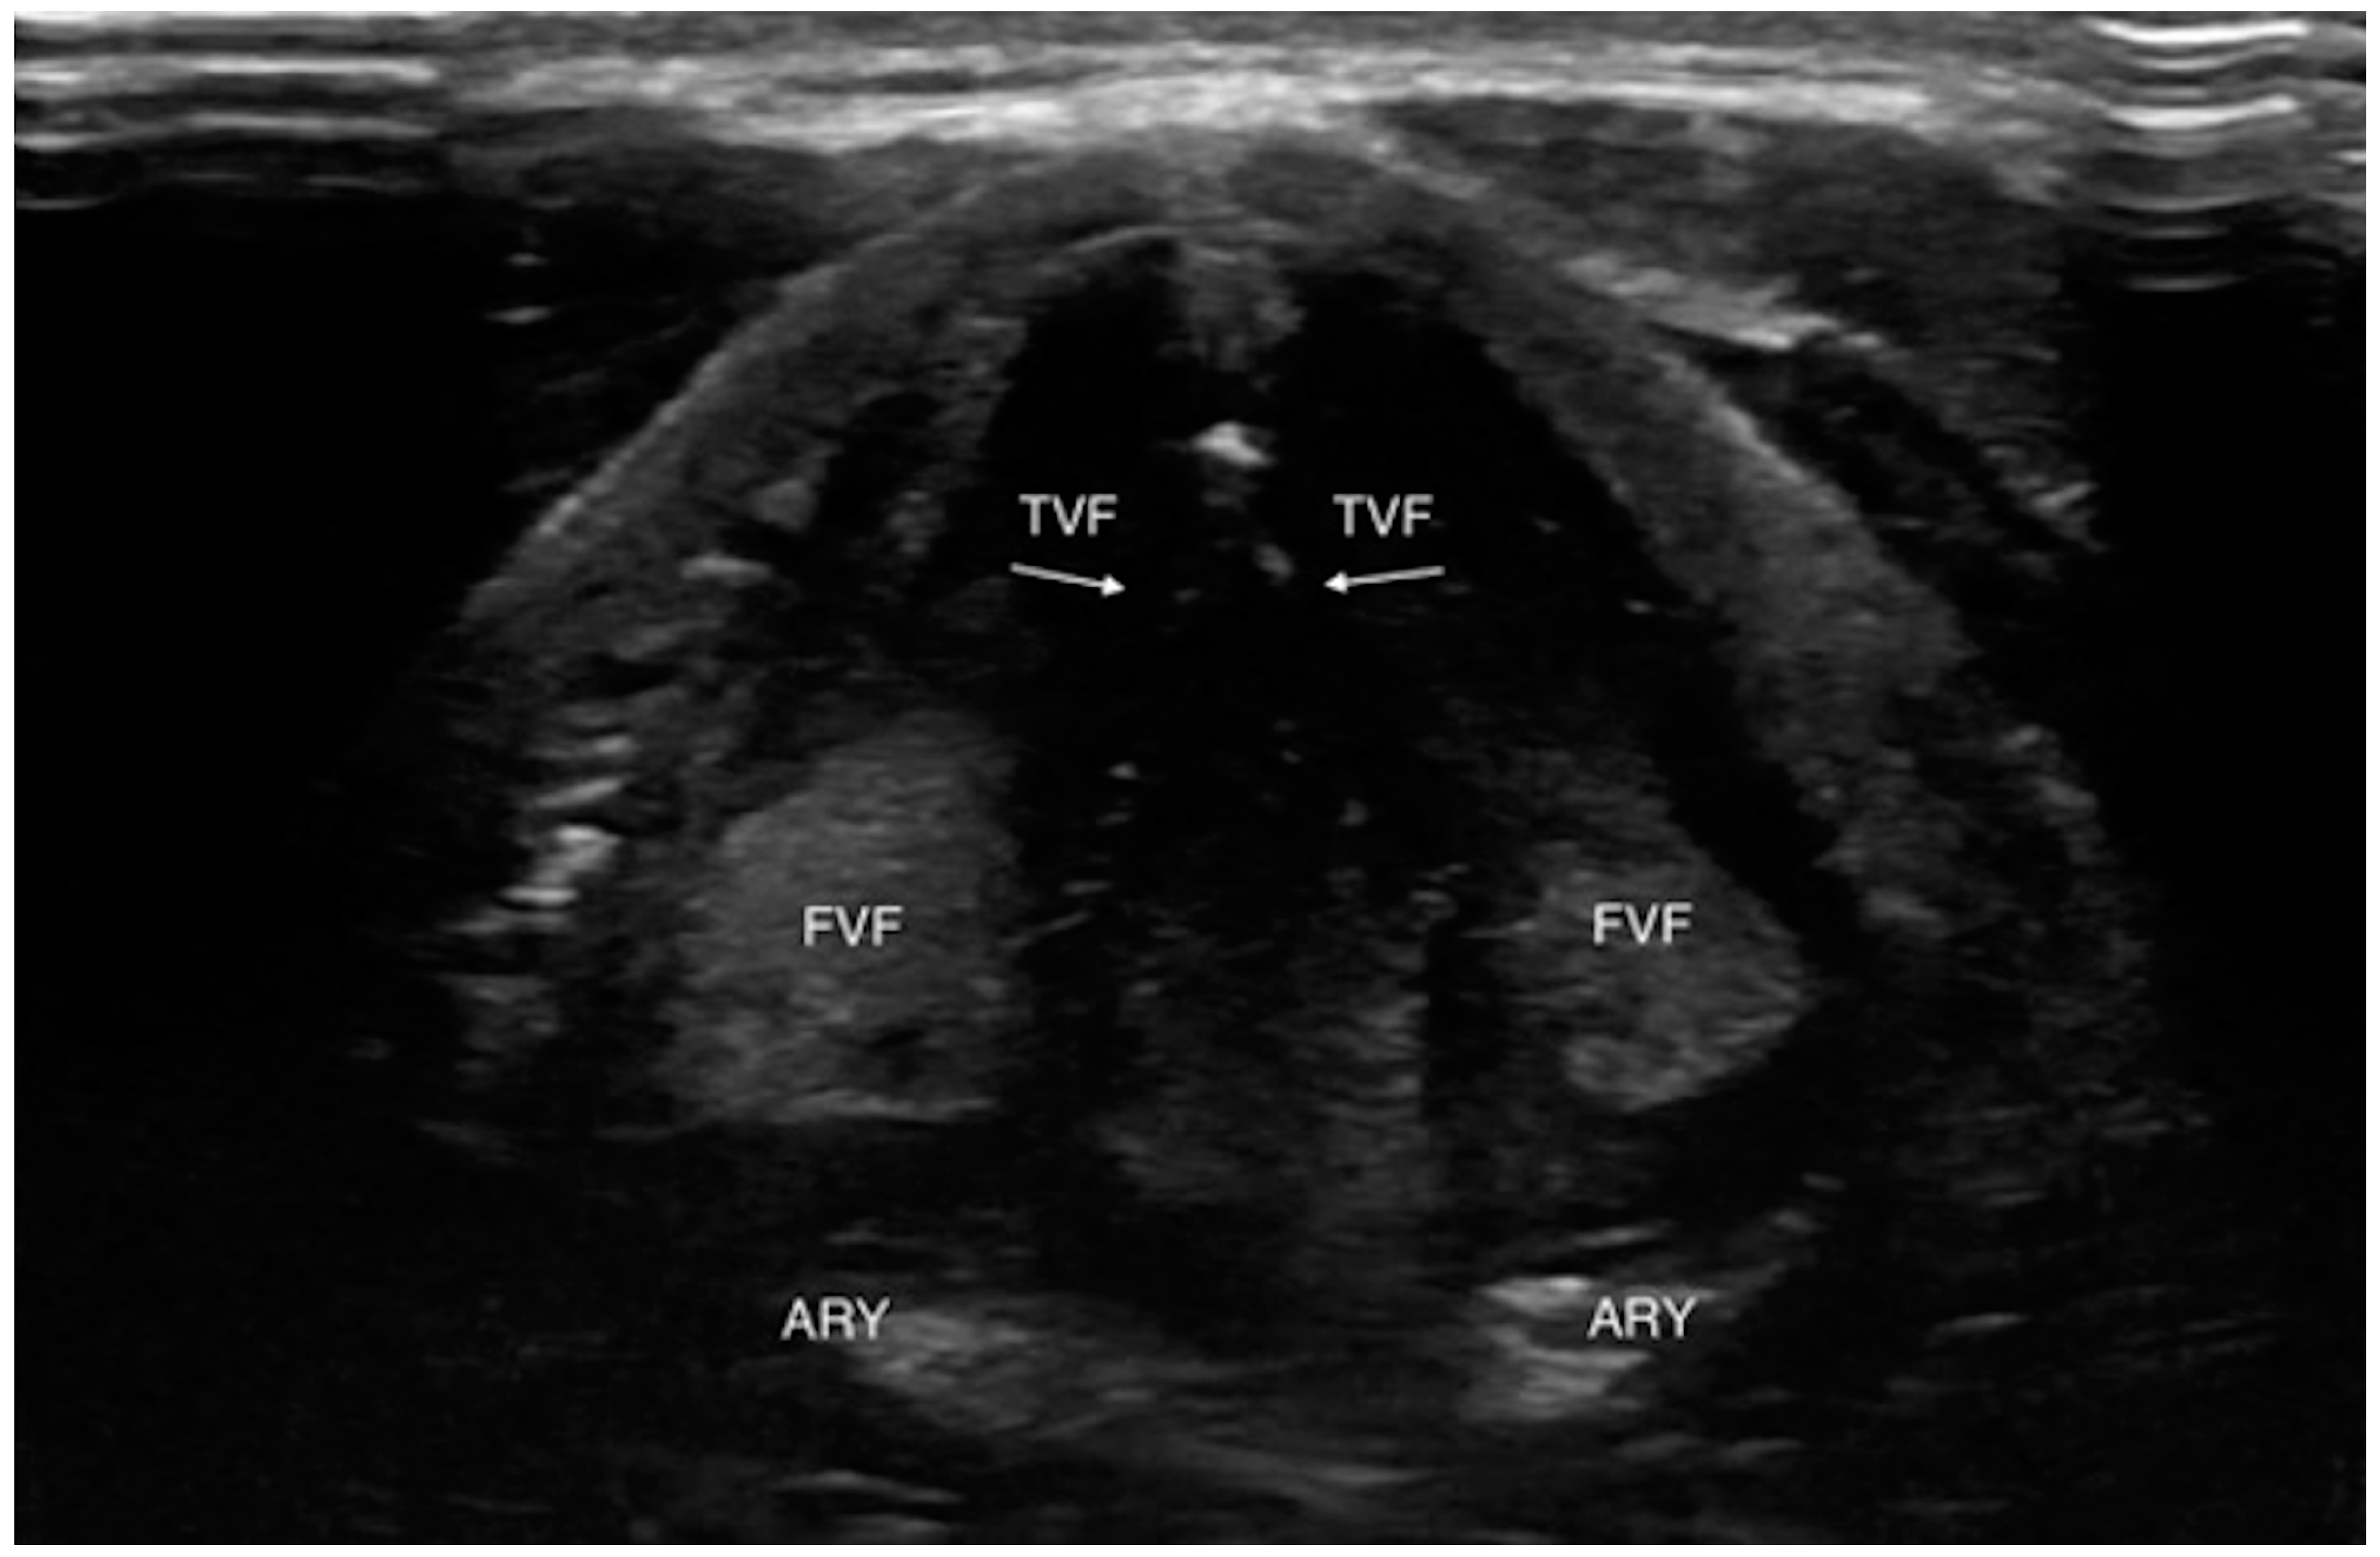

4.1.3. Laryngeal Edema Assessment Pre-Extubation

- Sutherasan, Y.; Theerawit, P.; Hongphanut, T.; Kiatboonsri, C.; Kiatboonsri, S. Predicting laryngeal edema in intubated patients by portable intensive care unit ultrasound. J. Crit. Care 2013, 28, 675–680. [Google Scholar] [CrossRef] [PubMed]

- Mikaeili, H.; Yazdchi, M.; Tarzamni, M.K.; Ansarin, K.; Ghasemzadeh, M. Laryngeal ultrasonography versus cuff leak test in predicting postextubation stridor. J. Cardiovasc. Thorac. Res. 2014, 6, 25–28. [Google Scholar] [CrossRef] [PubMed]

- Tsai, W.W.; Hung, K.C.; Huang, Y.T.; Yu, C.H.; Lin, C.H.; Chen, I.W.; Sun, C.K. Diagnostic efficacy of sonographic measurement of laryngeal air column width difference for predicting the risk of post-extubation stridor: A meta-analysis of observational studies. Front. Med. 2023, 10, 1109681. [Google Scholar] [CrossRef]